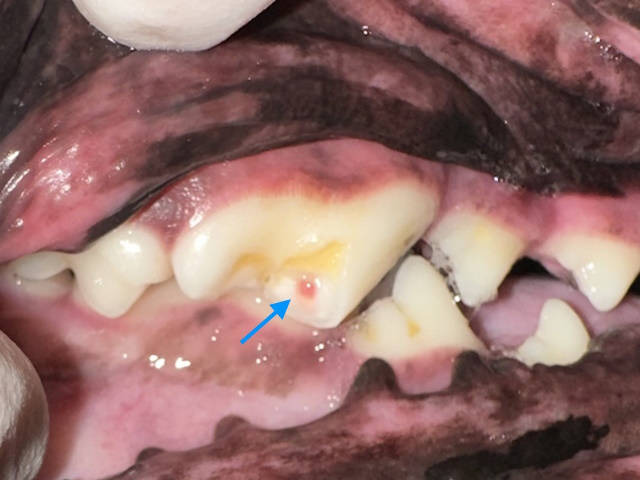

A complicated crown fracture that exposes the pulp. The pulp appears pink (blue arrow) indicating the fracture is recent.